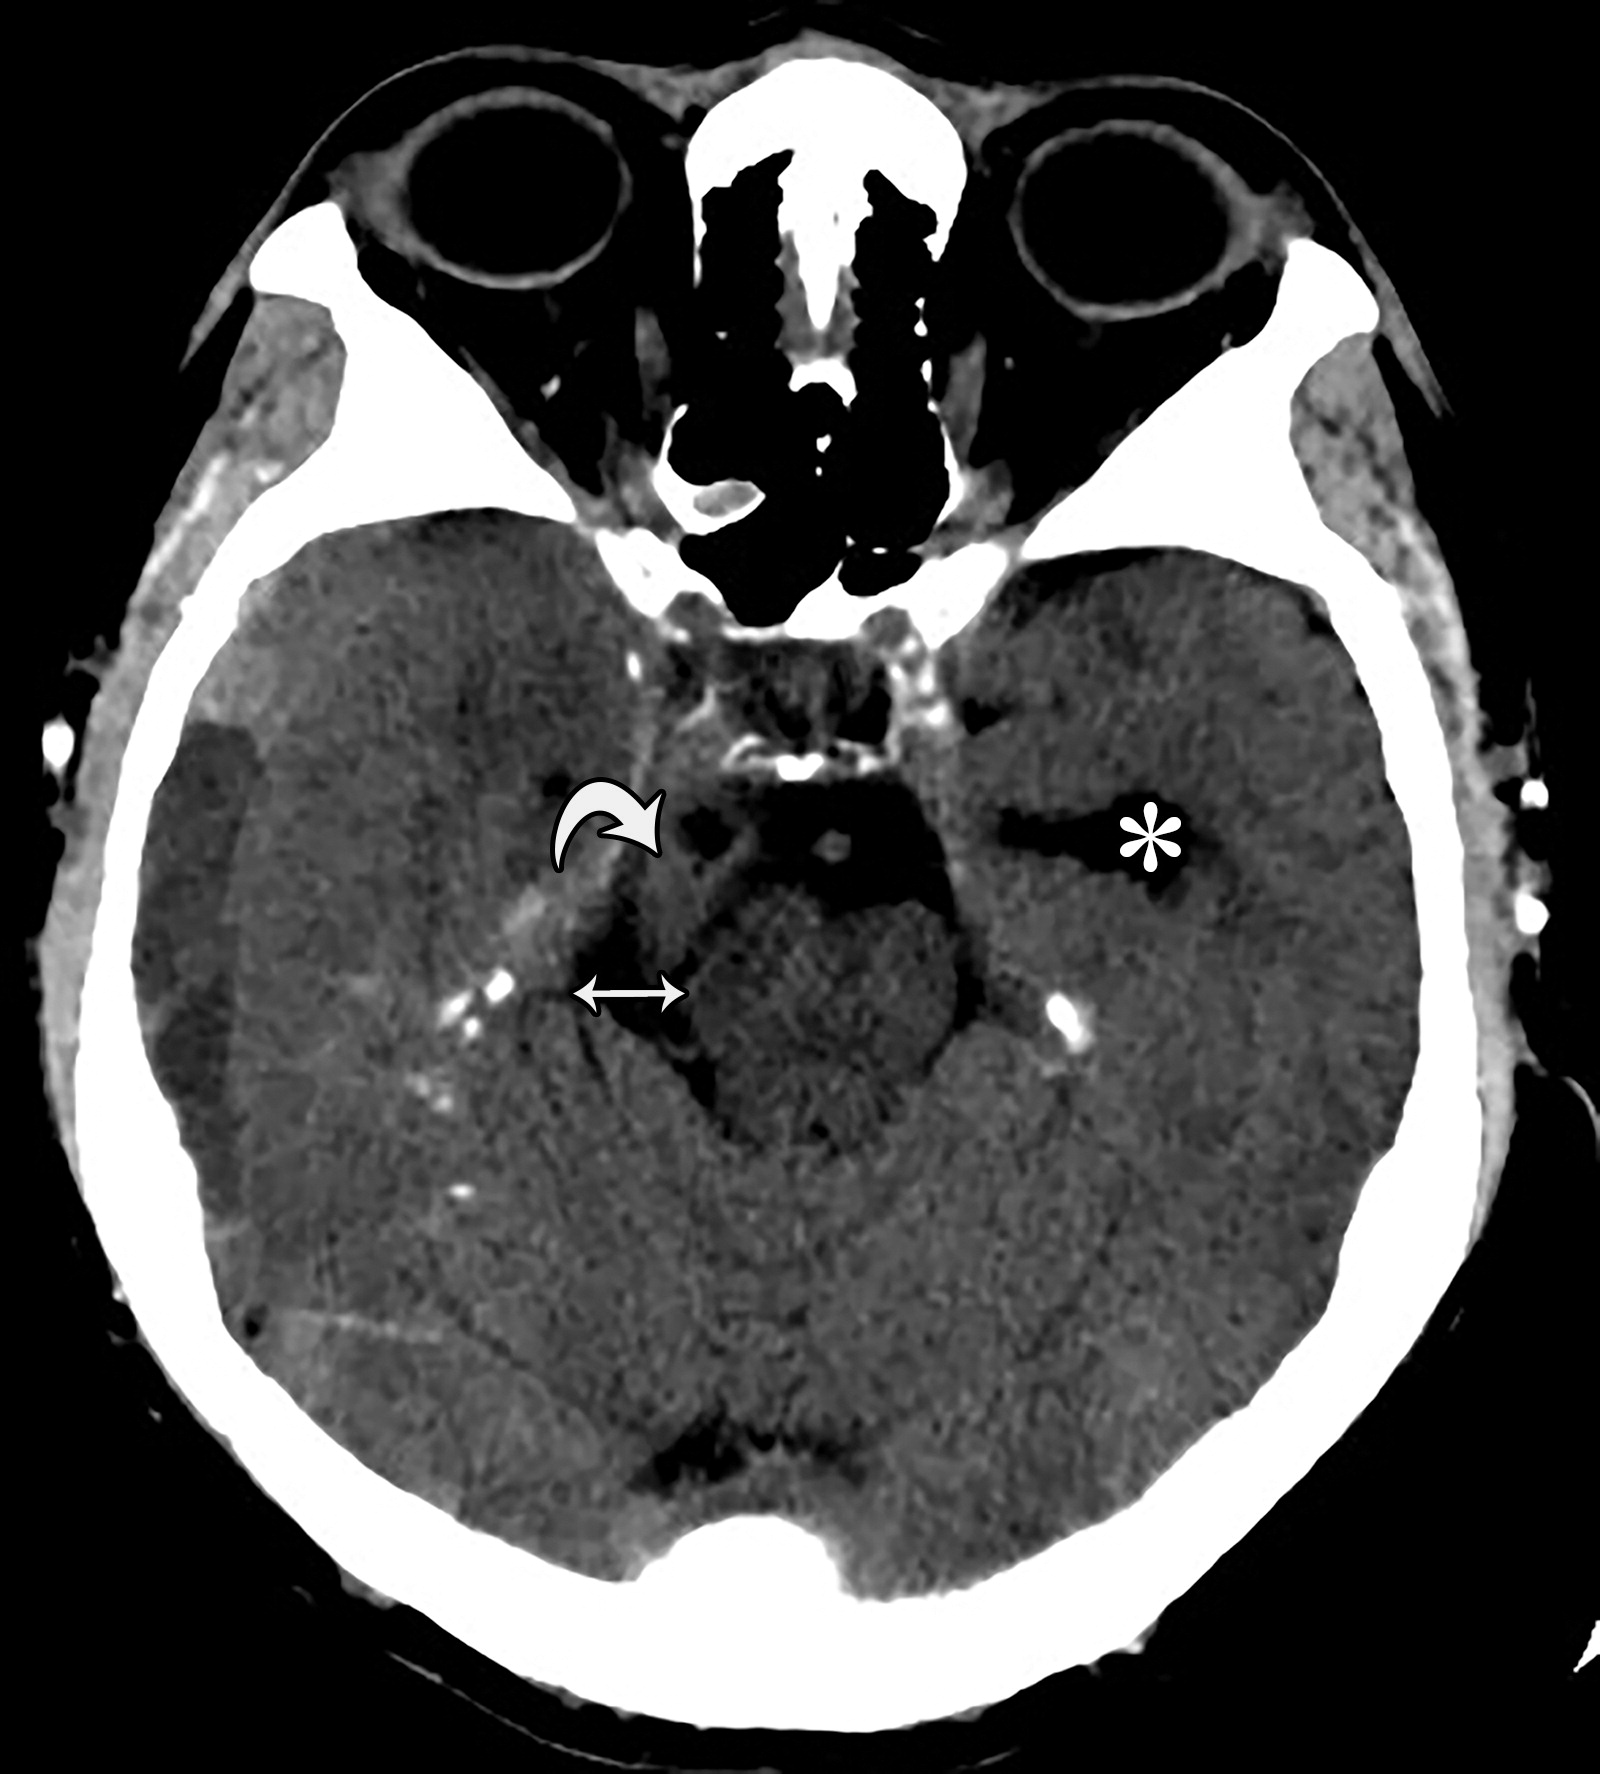

cbe1ef133c421383c74d5ed9defc43e3.jpeg

26岁男性,终末期肾病血液透析后硬膜下血肿,右侧瞳孔扩张,对光反射消失。钩回向下跨越小脑幕切迹(白色弯曲箭头),同侧的中脑周围池增宽(白色双箭头),对侧中脑周围池受压。注意对侧侧脑室的颞角增宽(*)。